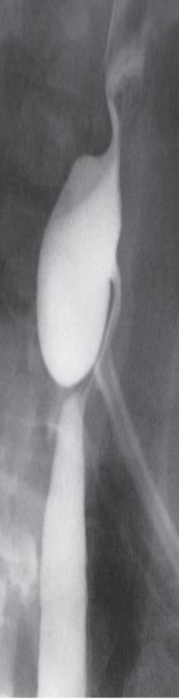

Barium swallow Pharyngeal pouch (Zenker’s diverticulum). The pouch lies behind the oesophagus, which is displaced forward

Dysphagia presentation

Oesophageal carcinoma

BARIUM SWALLOW

There is an irregular stricture

with shouldering at the upper

end.